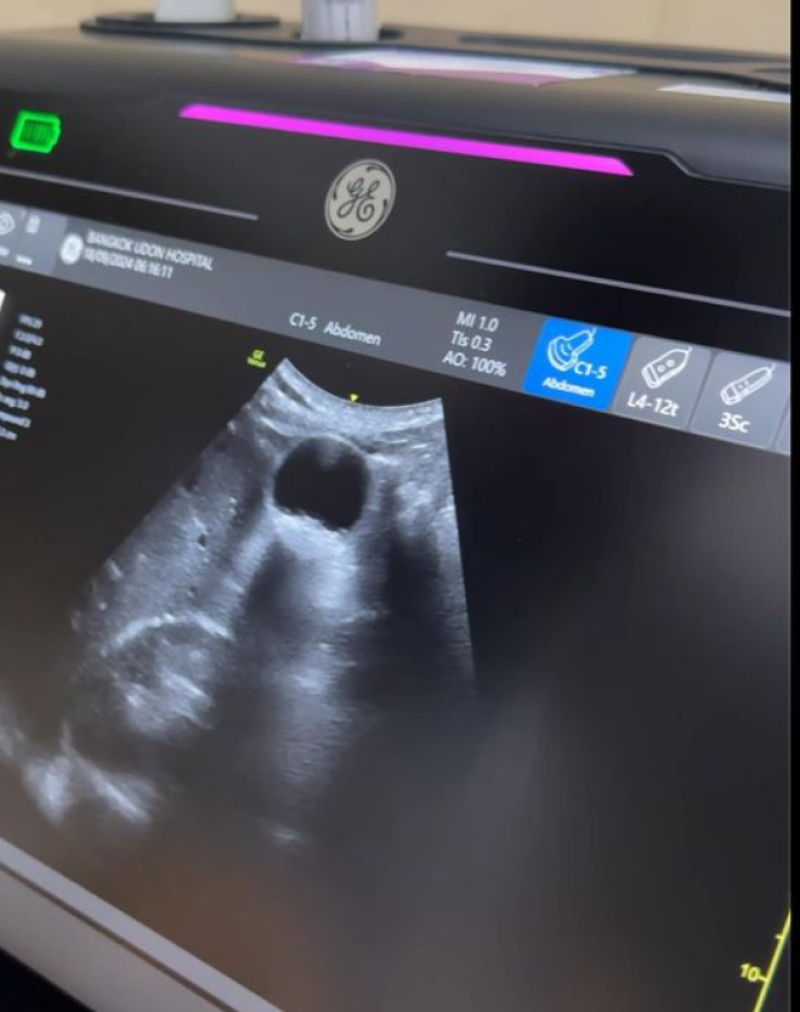

5555 ไม่ได้เป็นอะไรมากคับ แค่ปวดท้องบิดๆ ไม่แน่ใจจากของที่กิน หรือ นิ่วในถุงน้ำดี (เดี๋ยวไปเช็คหละเอียดอีกทีที่ กทม ) ตอนนี้ฉีดยาหละ หายปวด เมื่อคืนปวดตั้งแต่ตี 1 จน ตี5 กว่า ไม่ไหวหละ เลยมา รพ ดีกว่า โดนไป 1 เข็ม สบายไป วันนี้ ขอออกไปบูธ สัก 12.00 นะคับ เซ็นทรัลอุดร 18-24 กย ท่ามกลางแฟนๆส่งกำลังใจกันอย่างมาก